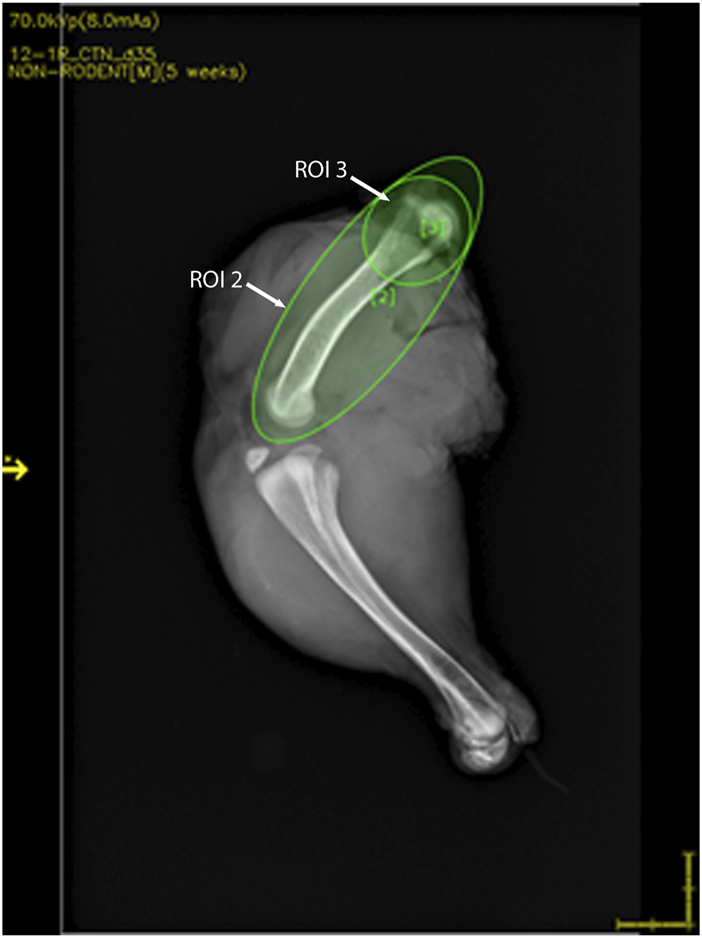

Chicken legs were thawed overnight at 4°C. Bone mineral analyses and 2D X-ray imaging were performed using a high-resolution DXA cabinet body composition analyzer (iNSiGHT DXA, Scintica, London, ON, Canada), with the region of interest for analysis being set to include the whole femur as well as just the proximal head (Figure 2). The DXA system utilizes a cone beam X-ray, which passes through the sample, and the attenuation of the X-ray is recorded using the detector below the sample. This process provides the body composition in the x, y, and z planes and produces a 2D X-ray image (Figures 3 and 4). The acquisition parameters were as follows: 5 s at 60 kV and 5 s at 80 kV, both at 0.8 mA, with a pixel resolution of 2,048 × 2,560. There were no filters applied.

FIGURE 2

DXA image showing the representative region of interest (ROI) locations. ROI 2 includes the whole femur, whereas ROI 3 includes the femoral head.